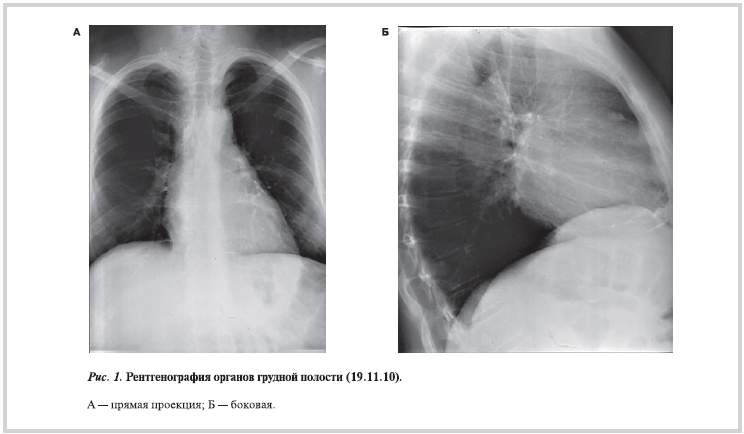

По данным МСКТ грудной и брюшной полостей отмечалась заметная положительная динамика — явления полисерозита практически не определялись (за исключением минимального количества жидкости в полости перикарда и правой плевральной полости). Внутригрудные ЛУ не увеличены в размерах, но увеличены количественно. Внутрибрюшные ЛУ не увеличены. Умеренное увеличение печени (рис. 8).